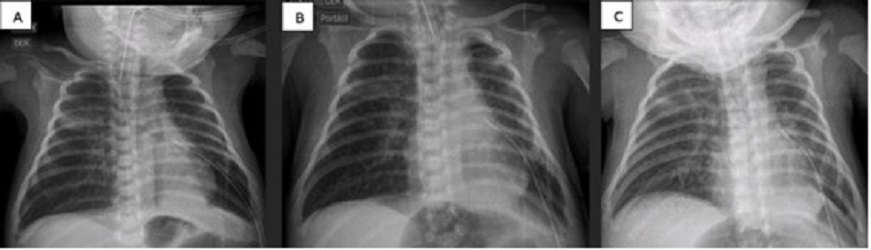

A 9-day-old female baby, born at 32 GW (1224 g), diagnosed with early onset sepsis, respiratory distress syndrome, and pulmonary hypertension. Placed on HFV with FiO2 at 94%. Due to right tension pneumothorax, chest tube placement was also required. Pneumothorax persisted for more than 5 days (labeled when air bubbles continue to drain nito underwater seal device for more than 5 days). ABPP was performed and improvement was noted at 48 hours (no bubbles, radiographic improvement, and decrease in ventilatory parameters). The chest tube was removed on the 19th day of life (Fig. 1).

Figure 2

A) Chest x-ray before pleurodesis. B) Chest x-ray 24 hrs post-pleurodesis. C) Chest x-ray 48 hrs post-pleurodesis.